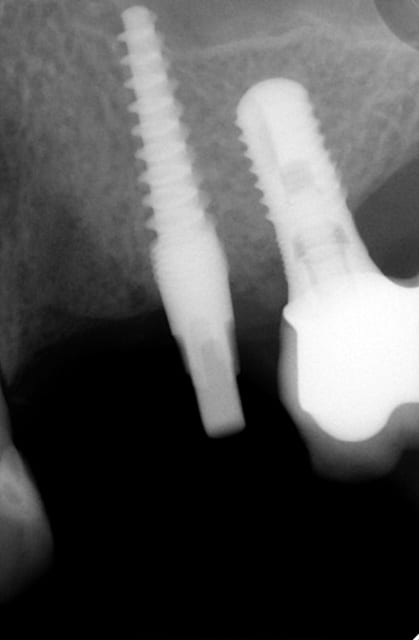

je t'explique : L'implant est un monobloc a tête carrée clavetée sur les 4 cotés la reconstruction prothétique se fait soit directement sur la tête soit par en utilisant des pieces intermediaires clavetées/cémentées que mes potes Allemands appelent les prep caps...Ca devient de la prothese conventionelle..Comme le prep caps a été placé le jour de la pose de l'implant..et que finalement faire une provisoire s'impose pas toujours..la gencive acceuille tellement bien le zicone ou le titane qu'a l'empreinte la limite usinée du prep caps peut etre recouverte..et alors.??.placer un fil ou mettre un coup de bis electrique..pourquoi faire?? on prends l'empreinte du pilier quitte à avoir un sous contour radiologique mais une excelente santé parodontale. Je te met quelques photos et ce week end je lance un post spécial sur cette technique ( Au moins 300 implants icononographiés de A à Z)

Ca marche aussi bien que les élévation de sinus en voie crestale..mais bon là aussi il vaut mieux faire vendre du biobidule ou laisser ces chirs a des "experts" vise l'augmentation osseuse obtenue sur l'implant en 16..:)